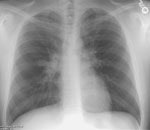

The patient shown below was a 27 year old male with complaints of recurrent pulmonary infection in the right middle lobe.

The PA chest radiograph revealed obscuration of the right heart border suggesting

infiltrate: